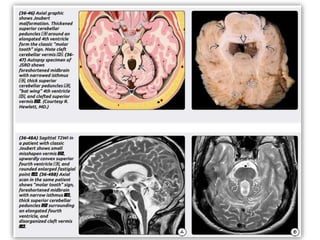

Pathology

Gross Pathology

โ€ข The most striking gross findings in DWM are (1) an enlarged PF with (2) upward

displacement of the tentorium and accompanying venous sinuses and (3) cystic dilatation

of the fourth ventricle.

โ€ข Vermian abnormalities range from complete absence to varying degrees of hypoplasia. In

DWM, the 4th ventricle choroid plexus is absent.

โ€ข DWM is frequently associated with other CNS anomalies. Almost two-thirds of patients

have gyral abnormalities (e.g., pachy- or polymicrogyria and heterotopic GM). Callosal

dysgenesis is common.

Microscopic Features

โ€ข The PF cyst in DWM is typically lined by two layers: an outer layer of pia-arachnoid and

an inner layer of ependyma.

โ€ข Occasionally, microscopic remnants of cerebellar tissue are present in the cyst wall.